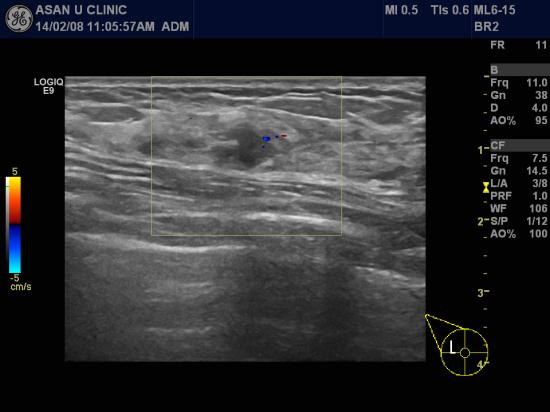

2012년 건강검진시 발견된 유방 결절소견으로 6개월 후 추적관찰 해보라는

권유받은 48세 여성분입니다.

여러 양성형 결절이 젊었을때부터 만져져서 크게 신경쓰지 않아

6개월을 훌쩍 넘긴 상태였고

본원 초음파 검사상 악성으로 의심되는 1.1cm의 결절이 우측 유방 상외측에 있어

조직검사하여

침윤성 유방암 진단되었습니다.